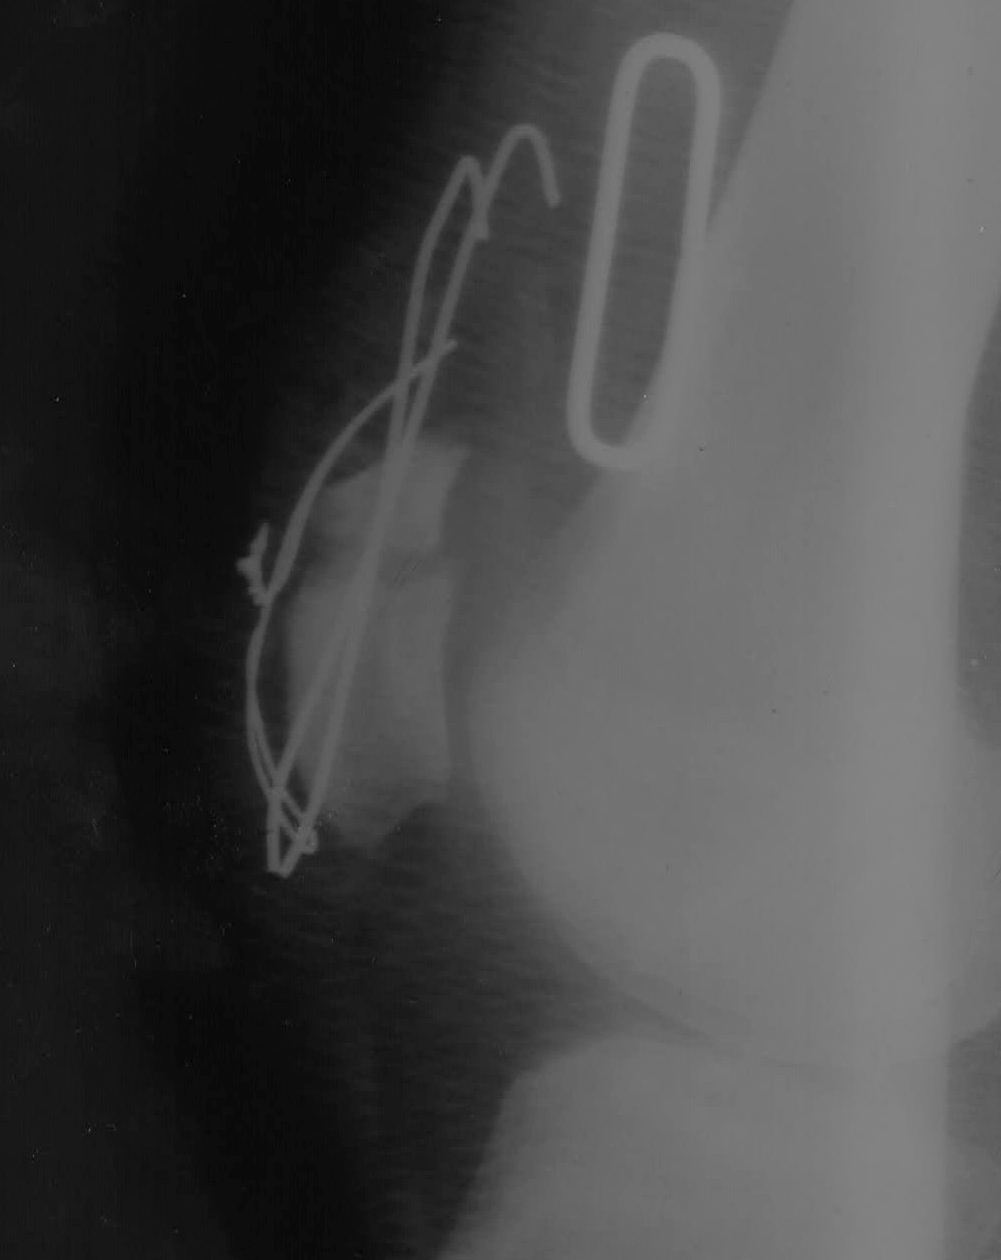

[Ortho] Рефрактура надколенника

Прогноз сращения надколенника и реабилитация

Пациент 25 лет 170 кг получил травму в марте, 2 недели лечился

консервативно для стабилизации состояния, в конце концов был

прооперирован в другом заведении в конце марта. Через 3 месяца

(25.06.2013) был удален металл, после чего даны рекомендации по

восстановлению. 2.08.2013 при передвижении на ровном месте, как

утверждает пациент, просто произошел резкий хруст и появилась боль в

области надколенника.

После рентгенконтроля и оценки повторного перелома было принять решение

(оперирующим хирургом) лечить в ортезе консервативно

Было показано оперативное лечение - последнее выполнялось мною

Отломки были максимально "освежены" от рубцово-измененных тканей,

тунелизированы (каждый пройден сверлом в 5-7 местах) и адаптированы

между собой

Имеется рентгенологический диастаз (хотя клинически "стянул" проволоку

максимально (3 раза перед этим лопала при пробе большего стягивания или

сгибания в коленном суставе больше 40 градусов))

После операции сустав в ортезе, осевая нагрузка дозированная на костылях

что рекомендовать, насколько долго носить ортез (боюсь за проволоку),

вообще каков прогноз сращения при такких ситуациях